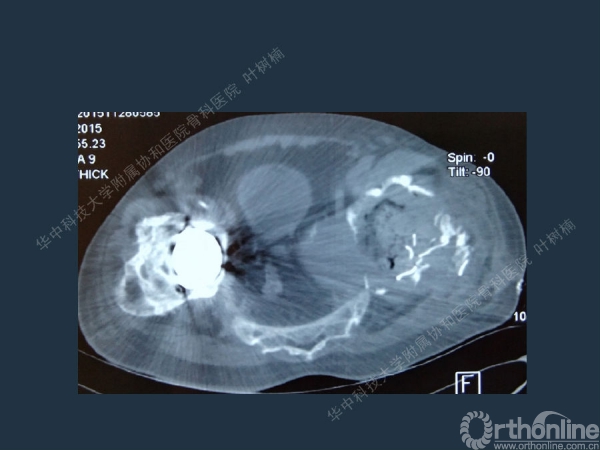

股骨侧翻修

髋臼缺损的处理